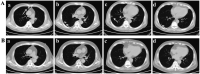

The relationship between antineutrophil cytoplasmic antibody (ANCA)-associated vasculitis (AAV) and lung cancer remains unclear. A 66-year-old man presented with pulmonary nodules. Histological examination of a specimen from computed tomography-guided percutaneous transthoracic biopsy revealed adenocarcinoma. The patient was treated using cryoablation and systemic chemotherapy. Sixteen months later, the patient presented with fever, nasal inflammation, recurrent lung lesions, elevated serum creatinine levels, and high levels of ANCA. Histological examination of a specimen from ultrasound-guided percutaneous renal biopsy revealed pauci-immune necrotizing crescentic glomerulonephritis. The patient responded to treatment, but granulomatosis with polyangiitis recurred and he later died. This case highlights the possibility of sequential AAV with lung cancer. Although this is relatively rare, further research is needed to better understand the association or pathophysiological link between lung cancer and AAV.